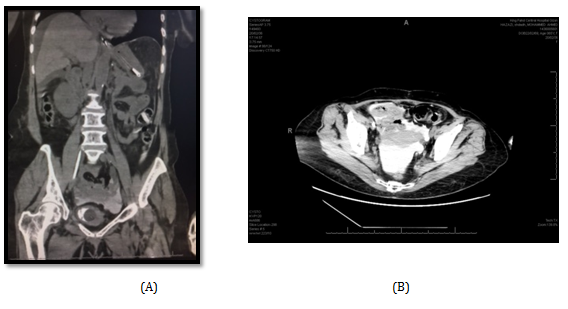

Post-operatively, The SPC was not draining well with persistent suprapubic urine leakage, so the patient was referred to our hospital 2 weeks following the primary surgery. On examination; patient was conscious, well- oriented with average general condition. Abdominal examination showed gapping of suprapubic wound with leakage of turbid urine; the SPC was not functioning well. A stone was felt in the bulbar urethra during perineal examination. Patient gave history of left nephrectomy 2 years before for a nonfunctioning kidney. Serum creatinine, BUN, HB, and WBCs were 64 mg/dl, 3.4 mmol/l , 9.9 gm, and 6640 respectively. Non- contrast CT showed no intraperitoneal fluid collection, right moderate hydroureteronephrosis, dilated left ureter with 2 stones in its lower end and 3 stones in the proximal bulbar urethra (Figure 1). Retrograde urethrocystogram showed a 3 cm stricture segment at the distal bulbar urethra and another annular stricture at the proximal bulbar urethra in addition to an urethral diverticulum in between containing the stone and grade 4 right vesico-ureteral reflux (Figure 2).

Figure 1: Non-contrast CT scan showing a big stone in the bulbar urethra and thick walled bladder.